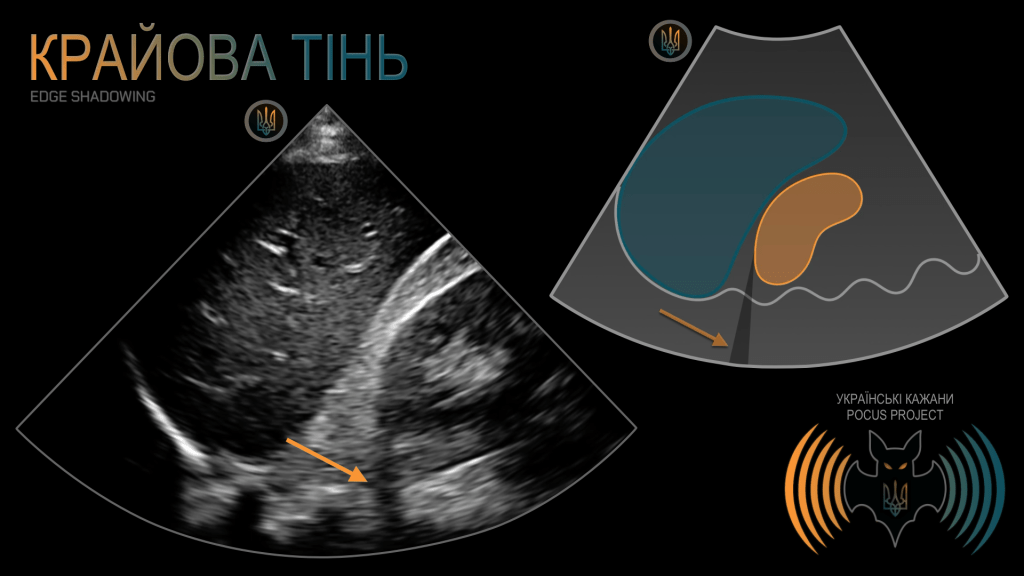

КРАЙОВА ТІНЬ: важливий артефакт, зумовлений рефракцією, тобто відхиленням ультразвукового променя від траєкторії, якою він «мав би» поширюватися. Слід пам’ятати, що УЗ-сигнал не завжди рухається прямолінійно. Таке відхилення найчастіше виникає, коли УЗ-промінь потрапляє на поверхню криволінійного відбивача, наприклад нирки, жовчного міхура або кровоносної судини. Іноді цей артефакт помилково інтерпретують як вільну рідину. У нашому прикладі видно артефактну чорну лінію, що тягнеться прямо від округлого полюса нирки. Звернімо увагу, що вона перетинає кілька анатомічних площин, яких вільна внутрішньочеревна рідина фізично не може досягти. Анатомічного сполучення з черевної порожнини через заочеревинний простір і далі за хребет не існує.